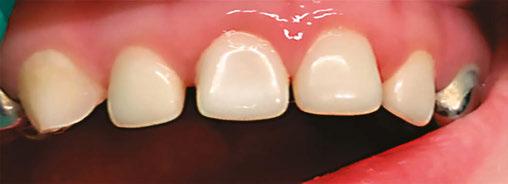

Several clinical solutions exist for primary anterior teeth with multisurface decay. Full coronal restoration of carious primary incisors may be indicated when caries is present on multiple surfaces, pulpal therapy is indicated, caries may be minor, but oral hygiene is very poor, or in a child with severe early childhood caries or a high caries risk diagnosis.1 Depending on the clinical scenario, a minimally invasive approach with the utilization of a high viscosity glass ionomer cement (HVGIC), with or without the combination of silver diamine fluoride (SDF) in a strip crown form, may pause the caries progression and provide an adequate clinical solution. Resin composite strip crowns have shown 80% retention rates and adequate parental satisfaction,1-4 although composite resin strip crowns have shown lower retention rates in teeth with decay involving three or more surfaces and particularly in children with a high caries risk4-6 (Figure 1). This could be from the continued high caries risk behaviors of the patient, as composite resin strip crowns in this population have shown to have increased inflamed marginal gingiva and gingival bleeding, increased plaque retention along the restoration, and loss of some restorative material.5,6

Alternatively, a resin-faced stainless steel crown provides a full coverage restoration with excellent retention.7 These crowns can serve as a full-coverage restoration with or without the resin facing, but the loss of resin facing can be a major esthetic concern for parents.7 Preformed pediatric zirconia crowns address many of the undesirable clinical outcomes of other restorative materials. Their biocompatibility, demonstration of excellent marginal gingival health, low plaque retention, high parental esthetic acceptance, and high survival probabilities make them an excellent clinical choice in the patient with severe early childhood caries.1,4,5,8-13

With parental interest increasing in esthetic treatment options for complex anterior caries, preformed pediatric zirconia crowns are becoming the treatment of choice for patients with a high caries risk or a severe early childhood caries diagnosis.14

This review discusses three clinical cases in which NuSmile® ZR (NuSmile, Houston, Texas) anterior pediatric zirconia crowns were the correct clinical decision in varying clinical scenarios.

A 2-year-old male who received full mouth dental rehabilitation (FMDR) under general anesthesia presented for his 6-month recall at 2-year post FMDR. He had significant plaque accumulations with poor oral hygiene along his existing stainless-steel crowns (SSCs) and non-treated teeth. Additionally, the patient had gingival bleeding and gingival inflammation

around these clinical sites. His anterior zirconia crowns showed healthy gingival margins with little-to-no plaque accumulations. This positive clinical finding is from the highly polished nature and biocompatibility of pediatric zirconia crowns. These restoration features limit plaque accumulations on the restoration and along the marginal gingiva, providing a localized positive aspect directly related to the choice of restorative material (Figure 2).

A 3-year-old female presented with pulpal necrosis and abscess on #E and pulpal necrosis on #F. Extraction therapy or pulpectomy was offered. The family was highly motivated to retain #E and #F. The pulpectomy was performed with 0.02 K-Flex hand files, 3% NaOCl with a lateral vented needle, obturated with Vitapex (Neo Dental International Inc., Federal Way, Washington), a premixed paste of calcium hydroxide and iodoform. The access was filled with a HVGIC sealing the pulp therapy and increasing the clinical success by minimizing the potential for bacterial contamination. NuSmile ZR anterior crowns were selected as offering a full-coverage, esthetic, cemented restoration with no polymerization shrinkage when compared to a composite restoration. Crowns were cemented with NuSmile® BioCem (NuSmile, Houston, Texas). This is clinically beneficial as the provider would want to cement a restoration that provides limited microleakage minimizing the potential for bacterial contamination.15-17 At 6-month follow up, lesion healing had occurred with healthy gingival margins and no plaque accumulations (Figure 3).

A 4-year-old female presented with existing Silver Modified Atraumatic Restorative Technique (SMART) style restorations on #D, #E, #F, #G, and caries on other teeth. These anterior lesions

had been previously treated using SDF and covered with a HVGIC in a strip crown form. Though her lesions were stable from the clinical success of the SDF and HVGIC, these restorations were starting to fracture and demonstrate loss of material. The family wanted a more esthetic treatment option that would have a longer survivability. Additionally due to her high caries risk nature, a full coverage restoration with NuSmile® ZR anterior crowns were a more ideal solution in stabilizing her extensive decay pattern and covering staining from SDF therapy (Figure 4).

Figure 3: NuSmile® ZR Crowns were selected as a cementable full coverage restoration. At 6-month recall, apical tissues were healed with excellent gingival health Figure 4: SMART style restorations that were definitively restored with NuSmile® ZR Crowns as an esthetic option to cover SDF staining

There exist multiple treatment solutions, but NuSmile® ZR anterior crowns provide a highly biocompatible, long lasting, and esthetically pleasing restoration. This is an excellent clinical choice for the high caries risk patient with severe early childhood caries.